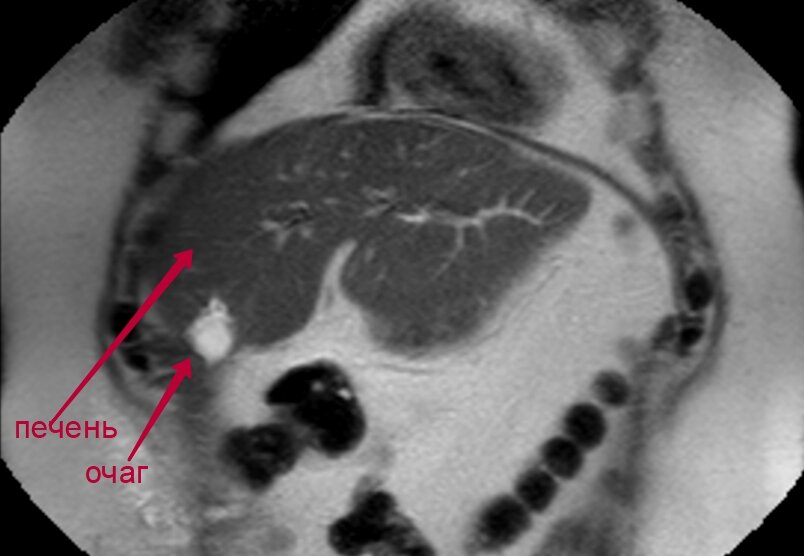

Снимок МРТ-обследования, на котором рентгенолог обнаружил подозрительный очаг

Рентгенолог описал очаг как наиболее вероятный метастаз

Дело в том, что операция, проведенная мне месяцем ранее, должна была удалить из моей печени все метастазы, которые в ней локализовались от моего рака прямой кишки. А тут я читаю в заключении, что… метастазы не только никуда не делись, но еще и стали крупнее. Черным по белому: «…с учетом МР-семиотики и динамики более вероятны гиповаскулярные mts… В сравнении с данными КТ от 5.11.2020 года — отрицательная динамика в виде увеличения ранее выявленных образований печени с их слиянием в VIII сегменте и возникновения нового образования в области V сегмента печени». Ну фсё — это конец! Какой еще я должен был сделать вывод, кроме как «операция не помогла, метастазы резко выросли, и мне осталось только попрощаться с родственниками...»

Пересмотр МРТ в Онкоцентре им. Блохина стоил почти 3 000 рублей, но оно того стоило. Опять же черным по белому: «Выявленные изменения соответствуют послеоперационным изменениям. Убедительных данных за прогрессирование основного заболевания не получено». Фууух, что и требовалось доказать: очаги, которые наш местный рентгенолог принял за увеличенные метастазы, оказались ничем иным, как послеоперационными рубцами. Уверен, что следующие МРТ-обследования это еще раз подтвердят.